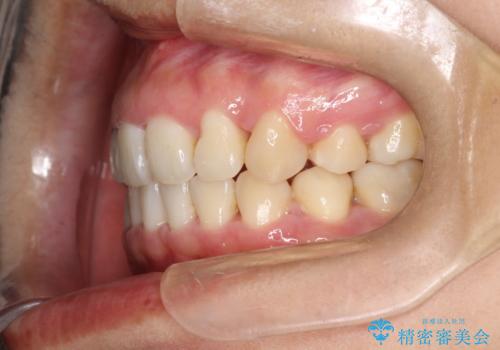

上下の歯のガタガタ ワイヤーでの抜歯矯正で整った歯並びへ

ガタガタが重度の方は抜歯が必要となることが多いです。

抜歯スペースを使って前歯を引っ込めることにより、口元の突出感も改善できました。